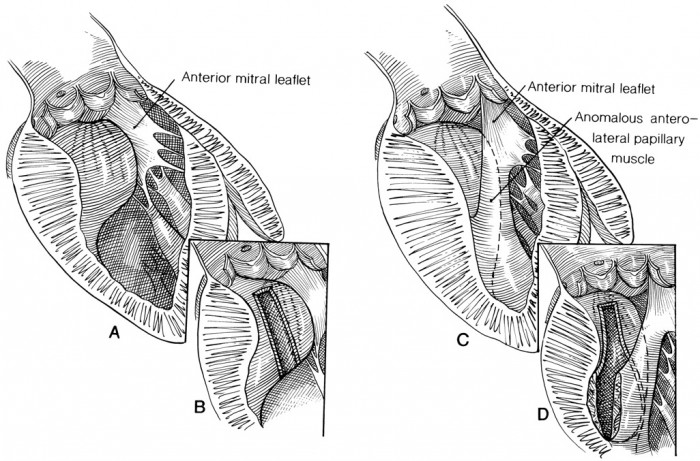

10 Septal Myotomy:

This surgical operation is performed to decrease the congealing of the heart muscles, which is a symptom of patients diagnosed with superior stages of a multifaceted sort of heart disease called hypertrophic cardiomyopathy. This is a difficult operation as it needs the patient to be put on cardiopulminary bypass, so that the surgeon can perform on a motionless heart. Indeed, this surgery can take from 3 to 6 hours, and the recovery period needs an accommodation in the Intensive Care Unit.